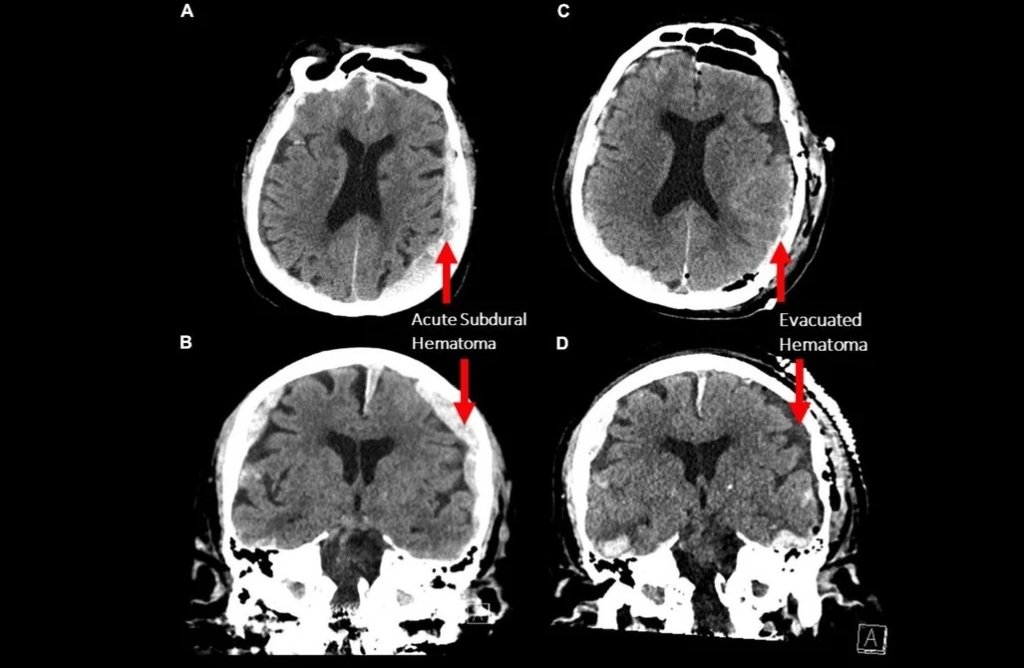

Μια επιστημονική ομάδα κατέγραψε τις τελευταίες στιγμές του εγκεφάλου ενός άνδρα που πέθαινε. Τα αποτελέσματα ήταν εκπληκτικά και δημιουργούν ερωτηματικά για το πώς και πότε πεθαίνει ο εγκέφαλος μας